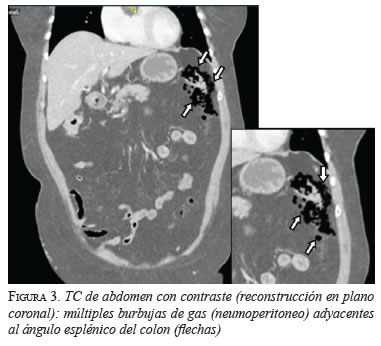

En las tres pacientes, la TC abdominal con contraste mostró el neumoperitoneo pericólico o localizado a menos de 5 cm del asa inflamada sin aire distante (figuras 2 y 3); dos presentaron divertículos en el ángulo esplénico, colon descendente y sigmoide, y una en el colon sigmoide únicamente.